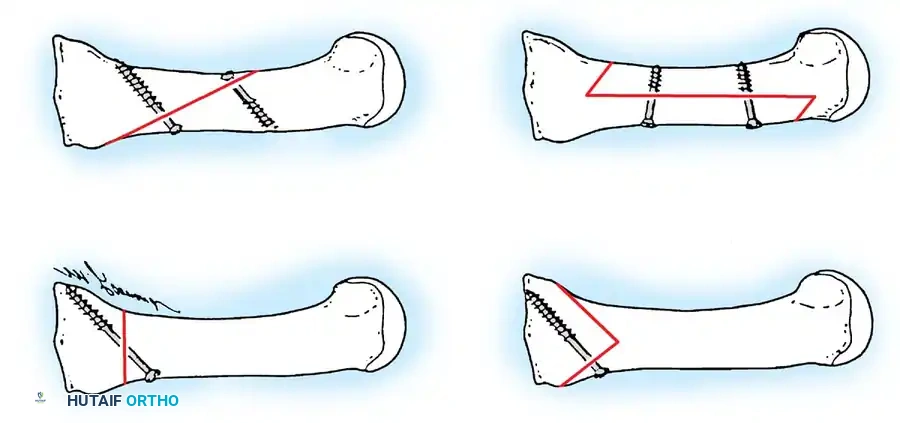

Presumably, the laterally displaced fi bular sesamoid, when pulled proximally by the lateral head of the relaxed fl exor hallucis brevis, pulls the fl exor hallucis longus laterally through the sesamoid apparatus, which encases it and contributes to recurrent hallux valgus. In addition, while reoperating after a failed Keller procedure, we observed a strong, linear, fi brous attachment of the fi bular sesamoid to the proximal phalangeal remnant (Fig. 78-32), which pulled the hallux into valgus when tension was applied to it. For these reasons, when the deformity is severe, the hallux and fi rst metatarsal maintain better alignment if excision of the fi bular sesamoid and lateral displacement of the metatarsal are added to the procedure. joint, lateral capsulotomy at the metatarsophalangeal joint, and lengthening of the extensor hallucis longus tendon. Hohmann recommended lateral displacement and plantar tilting of the distal fragment, following osteotomy at the metatarsal neck to correct hallux valgus. In 1945, a report by Mitchell et al. of 100 osteotomies gave the procedure his name. Since then, several authors have presented large retrospective reviews of the Mitchell operation to correct hallux valgus in adults and adolescents, with satisfactory results ranging from 74% to 94%. Gibson and Piggott described a peg-in-hole distal metatarsal osteotomy that differed from the Mitchell procedure in its use of a lateral plantar spike on the proximal fragment in place of the lateral spike on the distal fragment (as recommended by Mitchell). The nonunion rate has been negligible in all series of the Mitchell procedure, and recurrence of the deformity has been infrequent. The most troublesome complication has been metatarsalgia, attributable to dorsifl exion malunion of the distal fragment, excessive shortening of the metatarsal, or both (Fig. 78-33). In a long-term (average 21 years) follow-up study of 105 Mitchell procedures, Fokter, Podobnik, and Vengust found that the most common complication was recurrent hallux valgus with medial eminence pain. Their good-to-excellent results deteriorated from 97% at follow-up ranging from 2 to 11 years to 64% at follow-up ranging from 15 to 24 years, primarily because of recurrence of deformity with medial eminence pain. The use of a Kirschner wire for fi xation (instead of sutures) prevented malunion; all osteotomies healed in 6 weeks with only secondary displacement. Likewise, with the pegin-hole procedure, metatarsalgia has been the most common complication. Relief of pain, narrowing of the forefoot, and correction of the deformity have been achieved in most patients, however. A closing wedge osteotomy at the subcapital level of the fi rst metatarsal to correct valgus of the hallux also has its proponents. Although opponents emphasize that metatarsus primus varus is worsened, and recurrence of the valgus deformity of the great toe is likely, published series have not confi rmed this. Of 32 osteotomies reported by Peabody and 76 reported by Funk and Wells, no nonunions or signifi cant recurrences of the deformity were recorded. A popular osteotomy of the distal metatarsal is the chevron intracapsular osteotomy, which was described by Corless in 1976 as a modifi cation of the Mitchell procedure to correct the bunion associated with mild-to-moderate metatarsus primus varus. The procedure consists of two parts: (1) correction of metatarsus primus varus by a V shaped osteotomy in the sagittal plane through the metatarsal head and neck, followed by lateral shifting of the metatarsal head and trimming of the proximal fragment without internal fi xation (because of the inherent stability of the osteotomy) and (2) correction of the hallux valgus by suturing a previously raised fl ap of joint capsule into the abductor hallucis tendon. Several series of this osteotomy with adequate clinical follow-up have been published. Austin and Leventen reported, in 100 osteotomies randomly selected for analysis from a group of 1200, that no nonunions, osteonecrosis, or infections occurred. Hattrup and Johnson reported, in 225 feet (157 patients), that pain, shoe fi t, and cosmesis were improved in all but a few patients. Because their best results were in younger patients, the authors indicated that

the procedure probably should be reserved for patients who are younger than 50 years old. More recently, Trnka et al. reported 2and 5-year follow-up of 43 patients (57 feet) with chevron osteotomies; they found that outcome did not differ according to age: patients 50 years old or older had results as good as those in younger patients. Schneider et al. described consistently excellent clinical results after 112 chevron osteotomies in 73 patients; only one patient required a revision procedure because of recurrence of a painful deformity. Horne, Tanzer, and Ford modifi ed the technique of Corless and Johnson by placing the arms of the V -shaped osteotomy at a 90-degree angle (instead of a 45to 60degree angle) and by using a 2-mm drill hole as a marker at the apex of the intended V -shaped osteotomy. After reviewing the procedure in 76 feet, the authors concluded that the results of a chevron osteotomy are satisfactory, but that the technique demands attention to detail. They recommended it for the treatment of hallux valgus in patients with an intermetatarsal angle of more than 10 degrees, no degenerative metatarsophalangeal joint changes, and at least 60 to 70 degrees of fi rst metatarsophalangeal joint dorsifl exion. Meier and Kenzora reported satisfactory results in 86% of 41 patients (60 feet) after chevron osteotomy. Although they found a 20% incidence of osteonecrosis of the fi rst metatarsal head, a satisfactory result was not precluded by the development of osteonecrosis, even if the entire metatarsal head was involved or the subchondral bone had collapsed. The chevron distal osteotomy has been modifi ed to include an intracapsular-to-extracapsular extension of the osteotomy cuts, with the apex of the osteotomy at or slightly proximal to the center of the metatarsal head. The angle of the osteotomy is about the same (50 to 70 degrees), but the length of the two cuts can be modifi ed to accommodate the small amounts of bone removal needed to correct metatarsals with excessive valgus position of the articular surface of the metatarsal head. Some stability is sacrifi ced at the osteotomy site, however, and internal fi xation is recommended. Shifting the capital fragment laterally more than 5 to 6 mm is not recommended because of the loss of bone apposition. The primary advantage of the slightly more proximal placement of the osteotomy cuts is the correction of a wider range of deformities. Borton and Stephens modifi ed the chevron osteotomy by placing the bone wedge taken from the exostosis into the dorsal limb of the osteotomy to supinate, plantar fl ex, and distract the metatarsal. Internal fi xation was not used because distraction of the upper limb of the osteotomy tightened the soft tissues enough to provide stability. These authors suggested that supination and plantar fl exion of the metatarsal at the osteotomy are necessary to correct the pronation and metatarsus elevatus components of the hallux valgus deformity. In their series of 32 feet, the average correction of the hallux valgus angle was 21.7 degrees and of the intermetatarsal angle was 9.7 degrees. All but one of the 31 patients were satisfi ed with their results.